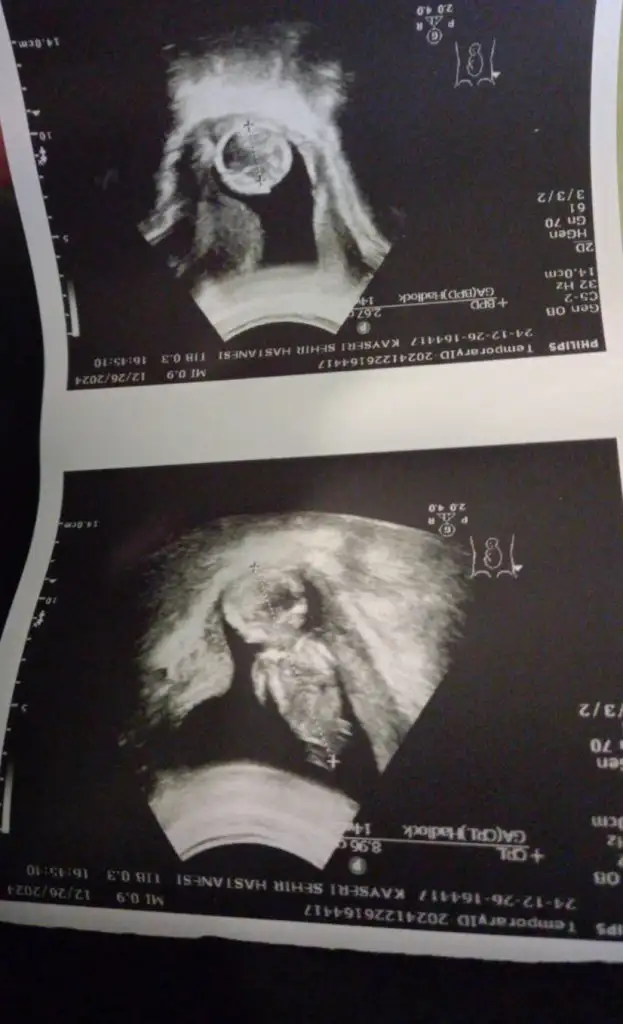

Rica edersem benimkinde bakar mısın lütfen 11 ve 9 haftalık resimler

• 1000926651.webp

1000926651.webp

18,2 KB · Görüntüleme: 55

• 1000924618.webp

1000924618.webp

20,4 KB · Görüntüleme: 53